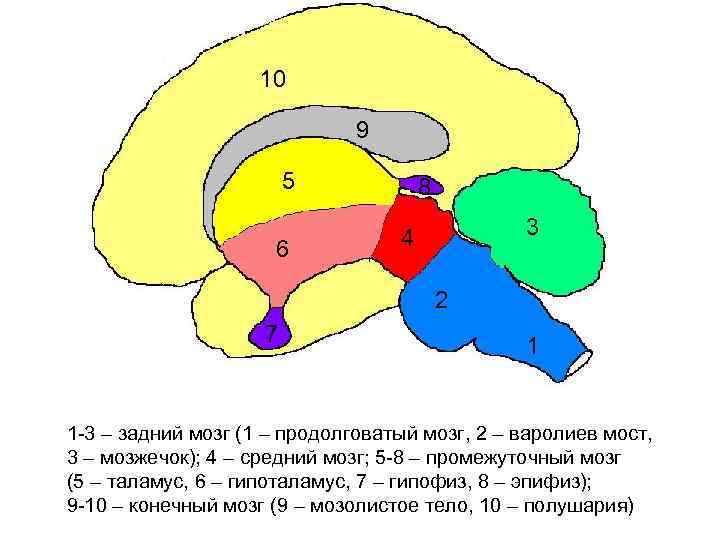

10 9 5 6 8 3 4 2 7 1 1 -3 – задний мозг (1 – продолговатый мозг, 2 – варолиев мост, 3 – мозжечок); 4 – средний мозг; 5 -8 – промежуточный мозг (5 – таламус, 6 – гипоталамус, 7 – гипофиз, 8 – эпифиз); 9 -10 – конечный мозг (9 – мозолистое тело, 10 – полушария)

10 9 5 6 8 3 4 2 7 1 1 -3 – задний мозг (1 – продолговатый мозг, 2 – варолиев мост, 3 – мозжечок); 4 – средний мозг; 5 -8 – промежуточный мозг (5 – таламус, 6 – гипоталамус, 7 – гипофиз, 8 – эпифиз); 9 -10 – конечный мозг (9 – мозолистое тело, 10 – полушария)